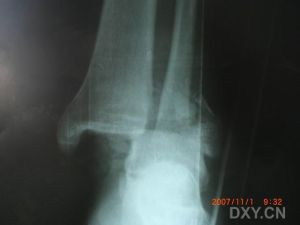

踝部骨折踝部受傷後,局部腫脹明顯,淤斑、出現內翻或外翻畸形,活動障礙,檢查可在骨折處捫局限性壓痛,踝關節正位、側位X線拍片可明確骨折的部位、類型、移位方向,對第Ⅲ型骨折,需檢查腓骨全長,若局部有壓痛。應補充照X線片,以明確高位腓骨骨折的診斷。

踝部受傷後,局部腫脹明顯,淤斑、出現內翻或外翻畸形,活動障礙,檢查可在骨折處捫多局限性壓痛,踝關節正位、側位X線拍片可明確骨折的部位、類型、移位方向,對第Ⅲ型骨折,需檢查腓骨全長,若局部有壓痛。應補充照X線片,以明確高位腓骨骨折的診斷。

踝部骨折Ⅰ型骨折為雙踝骨折,為恢復韌帶的張力,一般均應行切開復位,松質骨螺釘或由高分子材料製成的可吸收螺釘內固定8-12周。

Ⅱ型骨折為三踝骨折,內踝骨折採用松質骨螺釘或可吸收螺釘內固定,外踝骨折常需鋼板固定,影響脛骨1/3—1/4關節面的後踝骨折也需用松質骨螺釘或可吸收螺釘內固定。

Ⅲ型骨折除需對內踝行切開復位,內固定外,外踝或腓骨骨折也應行鋼板螺釘內固定,固定腓骨是保證脛腓下端穩定性的重要方法。